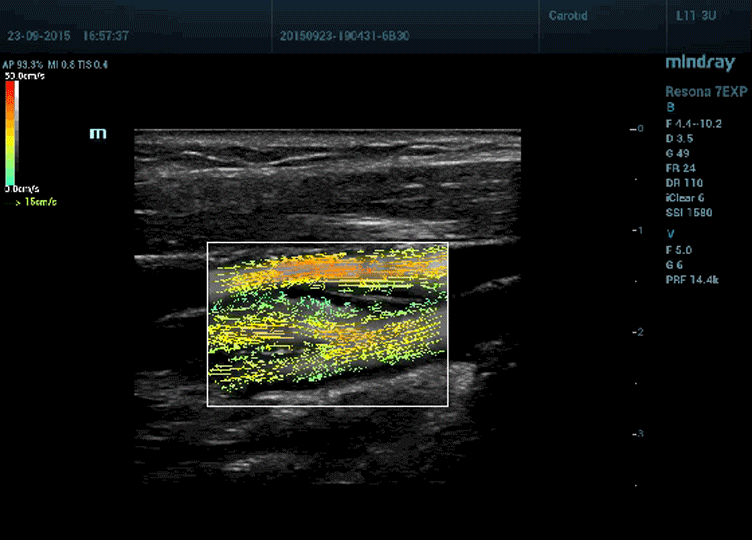

Resona 7’deki gelişmiş teknolojiler sayesinde, 3B tomografik görüntüleme yapılabilmektedir. Mindray’in V Flow teknolojisini içeren Resona 7, taranan atardamar, toplardamar veya kan damarı içindeki kan hücrelerinin hız büyüklüğünü ve yönünü doğru bir şekilde gösterebilir.

os14-s7@web

Mindray'in V Flow Uygulaması

Kan akışının hareketlerini görüntülemek için, okunması kolay okları kullanan sistem, hemodinamik değişiklikleri daha iyi görmek için, akış içindeki karmaşık hareketleri gösterebilir. Periferik kan damarlarındaki hemodinamik değişiklikleri dahi gösterebilir. V Flow ayrıca, plak birikimine dair erken gelişimleri saptamak için, Duvar Kesme Stresini belirleyip hesaplayarak bunu bir adım daha ileri götürür. Bu hassasiyet seviyesi ve bilgi açısından zengin veriler, 3B tomografik görüntünün oluşturulması için elzemdir.